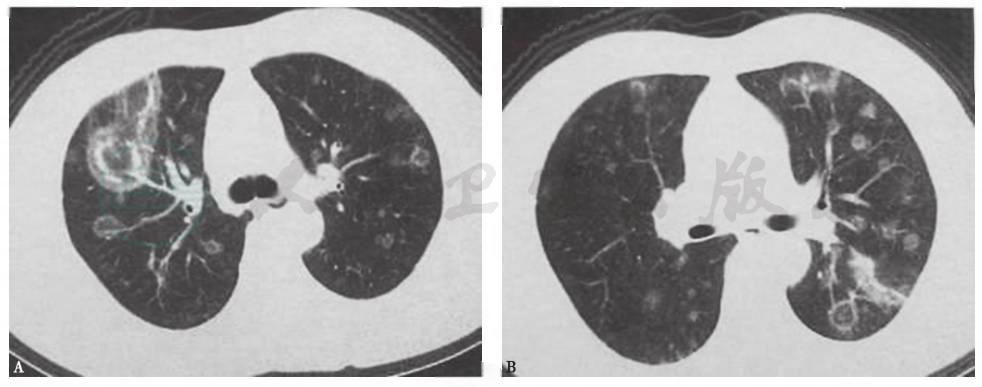

患者经口服糖皮质激素抗炎治疗后稳定恢复,复查胸部CT见图10~图12。

图10治疗8天时胸部CT表现

胸部CT见双肺原有病灶明显吸收,胸腔积液消失

图11治疗22天时胸部CT表现

胸部CT见双肺原有病灶明显吸收,部分病灶完全吸收

图12治疗3个月时胸部CT表现

胸部CT见双肺原有病灶完全吸收消失